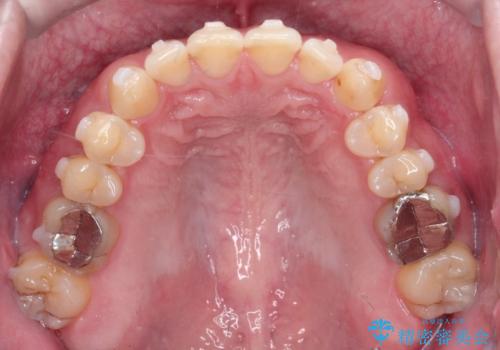

- 前歯の咬み合わせが気になるとのことで来院されました。

前歯が噛んでいない状態(開咬)のため、インビザライン矯正で改善することとしました。